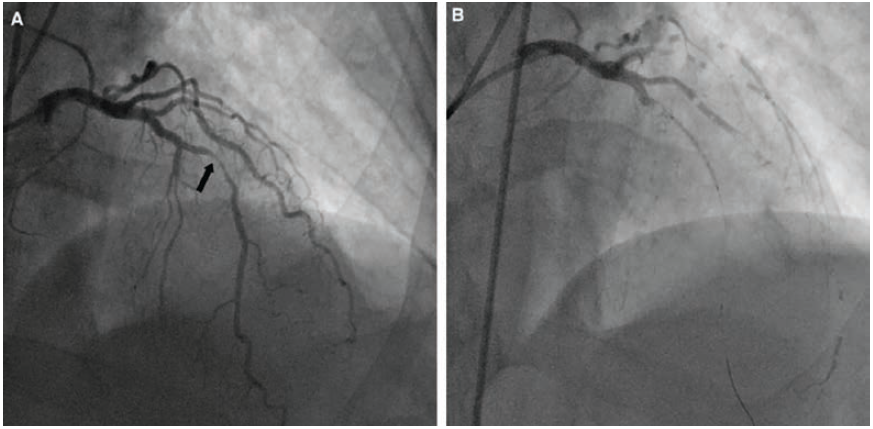

A coronary air embolism can be seen on angiography as a lucent spherical or circular lucency within the contrast-filled vessel or structure (Figures 2-3). The sequelae and pathophysiology of AEs arise from obstruction to blood flow, ischemia, and infarction from air entering the coronary arteries, brain, or other end organs resulting in reduced tissue perfusion. The lethal volumes of air in an acute bolus is approximately 0.5–0.75 ml/kg in rabbits and 7.5–15.0 ml/kg in dogs.4 The lethal dose for humans is theorized to be 3-5 ml/kg, estimated at 300-500 ml of gas introduced at a rate of 100 ml/sec.4 Air infusion rates of more than 1.5ml/kg/min are associated with bradycardia and cardiovascular decompensation.3 The rate of accumulation and patient position contribute to the lethality.4